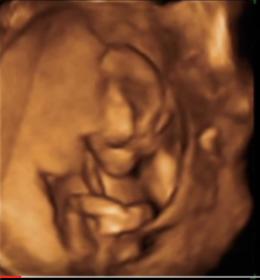

16 week guess 3d

I'm supposed to be team green but since day 1 everyone has said they think it's a boy. I'm 27 weeks now and feeling anxious to find out! Here are some pics from the 16 week scan video. The pics I have from the 20 week scan don't show anything at all. Do you think thats a penis or could it be the cord or something?

Attachment 31148